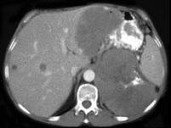

- 多项选择题女,38岁, 低热乏力并消瘦2月余,CT如图所示, 下列说法正确的是 ( )

A、左侧肾上腺区巨大的占位性病灶考虑为肾上腺癌

B、左侧肾上腺区巨大的占位性病灶考虑为嗜铬细胞瘤

C、左侧肾上腺区巨大的占位性病灶考虑为肾上腺腺瘤

D、肺内多发小结节病灶,考虑为肺转移癌

E、肺内多发小结节病灶,考虑为肺结核